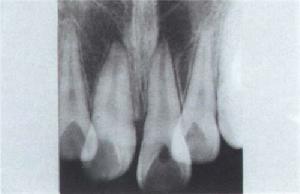

2、骨X光片

5、X線攝片檢查是否顯示骨膜增厚?